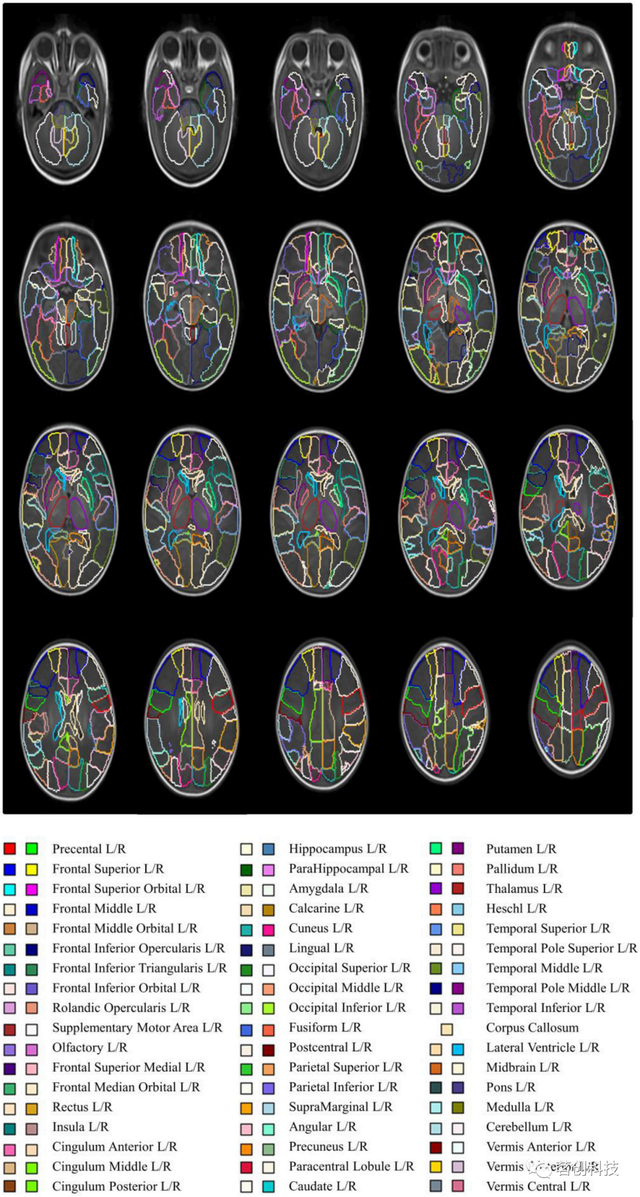

爱丁堡新生儿图谱(ENA33)

这是一组共同配准的T1和T2加权图像、DTI和33名正常发育的足月新生儿的分割图,这些新生儿在37-41周进行扫描。分割图由107个解剖区域组成,这些区域来自成人脑图谱(SRI24/TZO);

https://www.nitrc.org/projects/sri24。这在当前的婴儿大脑多图谱存储库中具有最精的细粒度。

http://brainsquare.org/

http://www.brainsimagebank.ac.uk/

来源:Parcellation of the healthy neonatal brain into 107 regions using atlas propagation through intermediate time points in childhood.